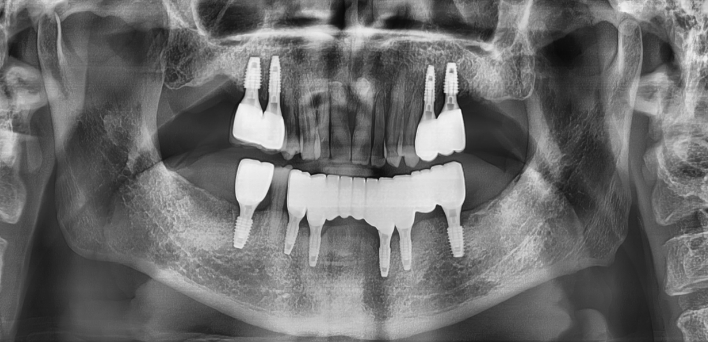

Before Before

2020.02.30

After After

※ 더서울치과의원은 의료법을 준수하며 위 케이스는 실제 환자의 동의를 얻은 사례로 치료 전, 후가 동일한 환경에서 촬영되었습니다.

환자 케이스에 따라 부작용이 발생할 수 있습니다. 이 부분은 의료진의 충분한 상담과 체크를 통해 예방하고 줄일 수 있습니다.

[임플란트 부작용] 수술 후 관리가 소홀할 경우 출혈, 주위염 등의 부작용이 발생할 수 있어 구강 위생을 철저히 유지하고, 정기적인 검진을 통해 상태를 점검하는 것이 중요합니다.

환자 특징

환자 특징01무치악 상태

환자 특징02수년간 무치악으로 지내심

임플란트가 불가능할것이라

생각하고 내원

위, 아래 6개씩 식립

디지털 풀아치 임플란트